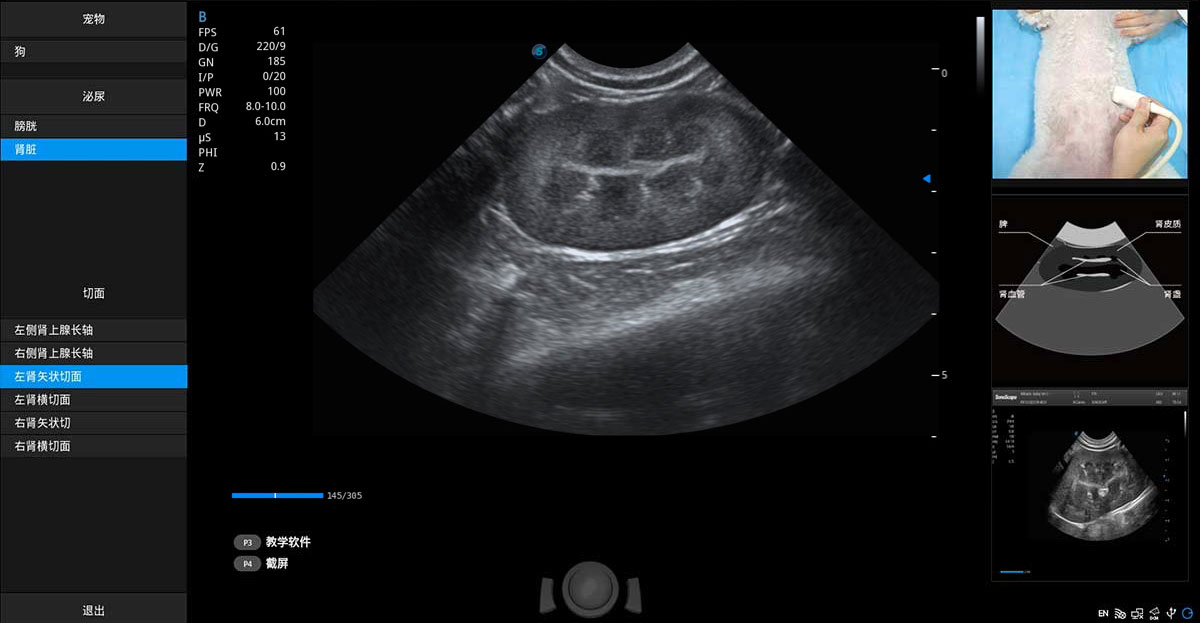

提供解剖示意图、标准超声图像、扫查手法图和操作者实时检查图像,指导操作者进行标准切面的正确扫查。

ProPet 70专为动物医生设计,对不同的动物体型和生理结构作出了针对性的优化。通过动物影像专用软件,可满足个性化的应用需求,帮助动物医生获得更精确的诊断数据。